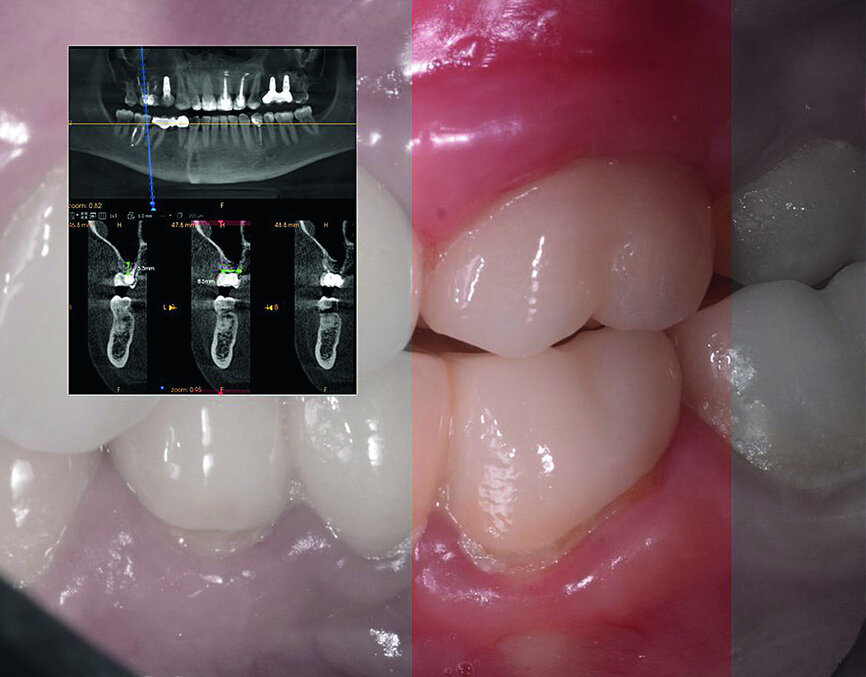

In November 2017, a 39-year-old female patient came to an initial appointment at White Clinic owing to tooth pain (tooth #16). A clinical and radiographic examination were performed, including a periapical radiograph, CBCT scan (Carestream 9500, Carestream Dental), and intra- and extraoral photographs (Figs. 1–3).

In the clinical and radiographic evaluation, it was observed that tooth #16 presented an invasive cervical resorption at the mesiobuccal root. The treatment plan established was dental extraction with immediate implant placement. The tooth had been previously re-treated endodontically and restored with a definitive ceramic crown. Due to the current situation of the tooth, although the protocol in White Clinic is to preserve teeth, it had indication for immediate extraction. Also due to the lack of time, our digital team was not able to produce a surgical guide for the implant placement. Therefore, the treatment plan included a surgical phase and a digital prosthetic phase.

In March 2018, four months after the surgery, the prosthetic phase was started. An impression was taken with an intraoral scanner (CS 3600, Carestream Dental) using scan bodies for an impression at the implant head (MegaGen; Figs. 11a & b). The information was sent to the Anatomic Lab, where a crown was designed using a CAD programme. After the design of the crown had been finished, the information was sent to a milling machine (Amann Girrbach) and the crown was milled (Fig. 12). One week after the preparation, the definitive crown in monolithic zirconia was attached and the occlusion tested using T-Scan technology (Tekscan; Figs. 13a–c & 14).